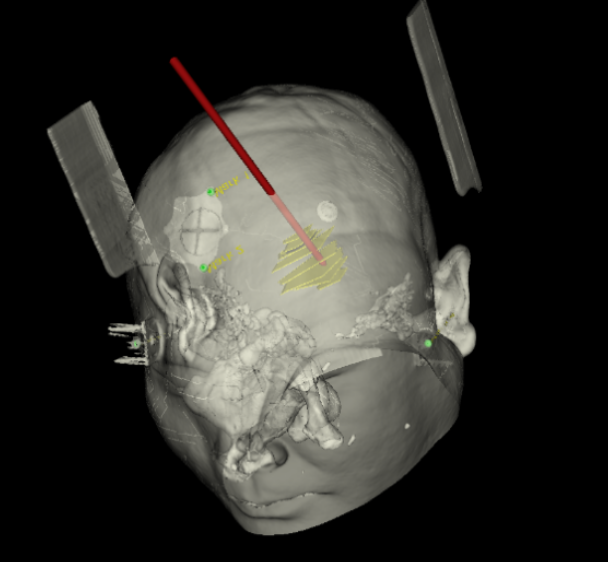

手術(shù)日當(dāng)天,醫(yī)生團(tuán)隊(duì)通過(guò)手術(shù)計(jì)劃系統(tǒng)為患者制定手術(shù)靶點(diǎn)及最安全的入顱路徑,隨后將手術(shù)規(guī)劃導(dǎo)入手術(shù)室的機(jī)器人當(dāng)中。

術(shù)前團(tuán)隊(duì)討論手術(shù)規(guī)劃

術(shù)前韓帥醫(yī)生使用“睿米”制定手術(shù)規(guī)劃

手術(shù)規(guī)劃在機(jī)器人軟件上制定完成